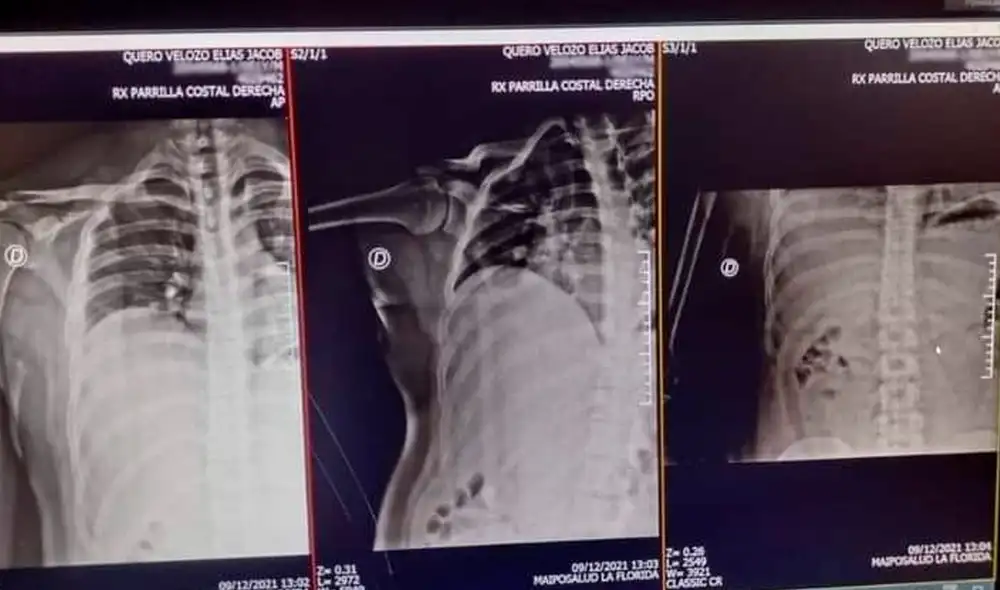

Una vez que Quero obtuvo prisión domiciliaria, fue visitado por especialistas que lo examinaron y le tomaron una radiografía que mostró que los golpes le provocaron una fractura en las costillas del costado derecho, además de una hemorragia interna.